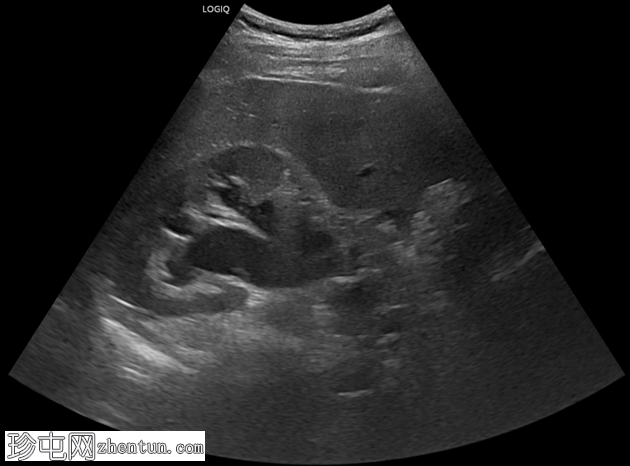

超声

检查

斜位

纵位

右侧中段输尿管结石,大小约1厘米,呈高回声,伴有声影,并可见闪烁伪影,导致中度右侧肾积水。